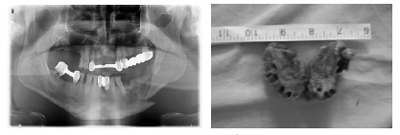

За период с октября 2009 до февраля 2012 к нам обратились 49 больных с “крокодил“-ОНЧ, все мужского пола, в возрасте 24-53 лет, т.е. все в тру-доспособном возрасте. Больные к нам обращались 1-24 месяцев после начала заболевания, предъявив следующие жалобы: боль в области поражения (40 больных-81,6%), отек окружающих мягких тканей (35б.-71,4%), оголение кости в полости рта (46б. -93,9%), наличие свищей в ЧЛ области (21б.-42,9%). Все больные отмечали применение наркотика “кро- кодил“ (дезоморфин), срок применения которого составлял 2-36 месяцев. Некоторые из них продолжали применение наркотика в момент исследования. У 48 больных диагностирован гепатит С (97,9%), у одного кроме гепатита С выявлен еще и гепатит В (2%), у 5 - ВИЧ (10,2%), у 7 - туберкулез легких (14,3%), у 6 -сахарный диабет (12,24%), только у одного больного (2%) не было обнаружено никаких хронических и инфекционных заболеваний в момент обследования.У больных были обнаружены 81 очаг ОНЧ. 72 очагов (88,9%) образовались после удаления зуба (зубы были удалены стоматологами по месту жительства,некоторые подвижные зубы были удалены больными или самопроизвольно выпали). Не исключено, что зубы были удалены уже из некротизированной кости. 8 очагов ОНЧ (9,9%) образовались самопроизвольно (в этих случаях причинами образования ОНЧмы считаем некачественные съемные и несъемные протезы, некачественное эндодонтическое лечение,периодонтиты, пародонтиты, микро- и макро травма слизистой оболочки полости рта, анатомические особенности челюстных костей (экзостозы, торусы),плохая гигиена полости рта). В одном случае (1,2%)ОНЧ развился в областинеправильно сросшегося перелома нижней челюсти (со слов больного, после получения травмы он не обратился в специализированное учреждение для получения квалифицированной медицинской помощи по поводу перелома нижней челюсти).Травму больной получил около 3,5 года до применения наркотика “крокодил“ (рис. 4).

Рис.4. Ортопантомограмма больного Р. Картина неправильно сросшегося перелома и диффузной резорбции кости нижней челюсти слева

Рис.5. Резецированный участок верхней челюсти, виден некроз твердого неба